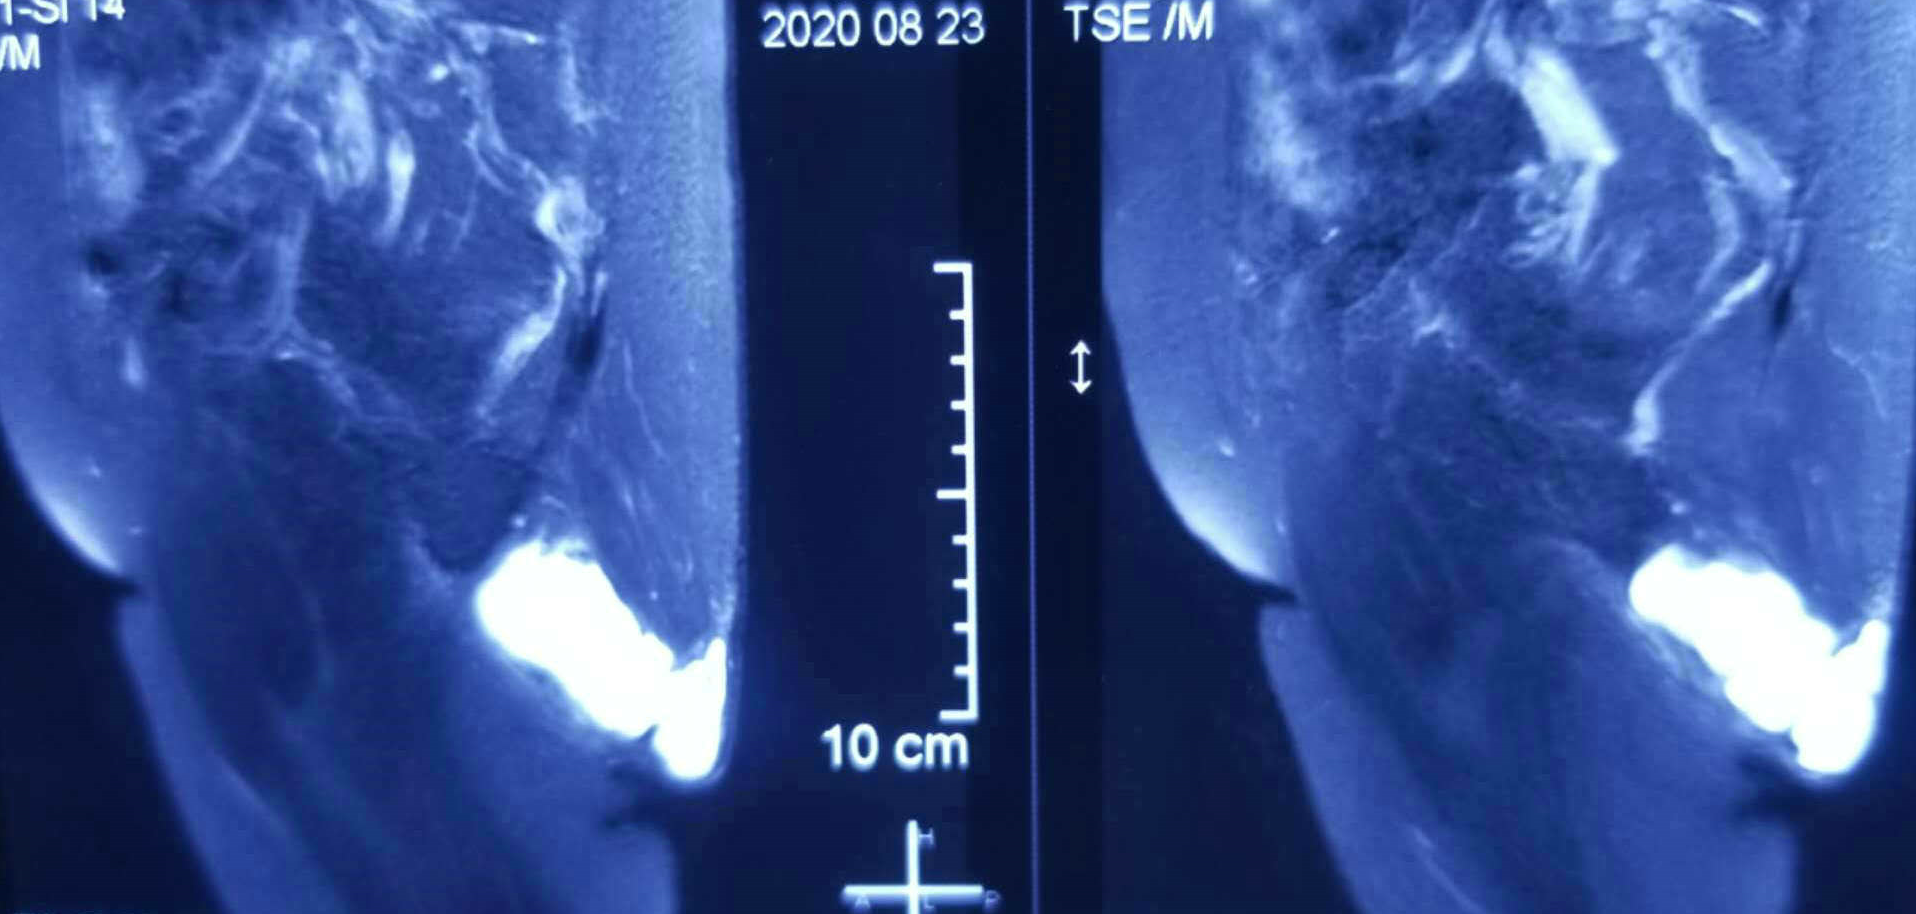

双髋矢状面MRI

该病例属罕见病例,患者病变范围较大,涉及双侧臀部皮下、深及坐骨结节及肛门肌群旁,发展迅速,并引起相应压迫症状,手术适应症明确。患者因严重双膝类风湿性关节炎导致近年行走功能基本丧失,主要以双手撑地,臀部着地方式移动身体,日常生活以坐姿为主,致使坐骨结节被迫“代步”,长期摩擦导致局部滑囊炎,进而产生巨大囊肿,因此,“以臀代步”为主要病因。经我院手术治疗,彻底切除了囊肿的发源处相关组织,解除对周围器官的压迫,术后患者不适症状明显缓解。预防复发的关键在于积极治疗双膝类风湿性关节炎并严重内翻畸形,改善步态。